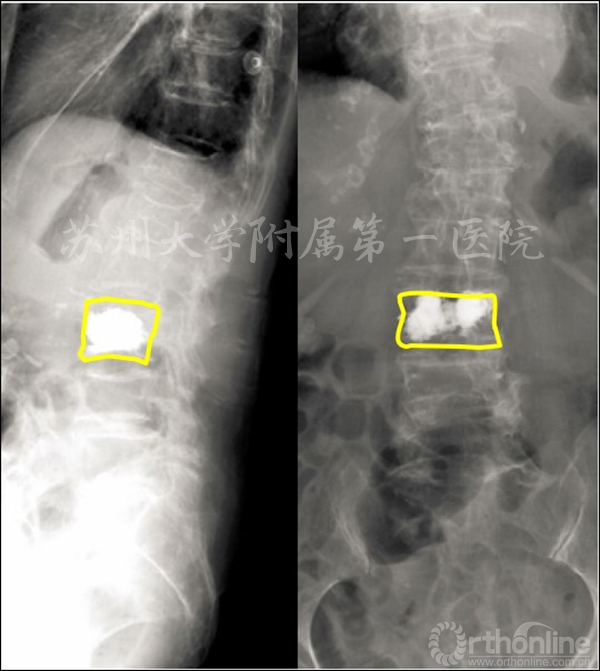

二、提出“OVCF骨不愈合”概念和诊断标准,并建立了二次调制灌注封堵和骨水泥-骨锚合技术治疗OVCF骨不愈合,既实现了缺损封堵,又保证了骨水泥在椎体内的弥散锚合,使以往未被认识或放弃治疗的患者得到了安全有效治疗。

患者夏×,女性,97岁,腰3为疼痛责任椎体,行KP治疗

杨惠林教授团队仔细分析夏阿婆的症状、体征和影像学检查,通过创新技术,最后判定只有腰3是导致夏阿婆疼痛的罪魁祸首,即“疼痛责任椎体”。仅对腰3骨折行微创KP手术治疗后,夏阿婆腰背疼痛迅速缓解,术后1天即下地行走,3天出院。前不久,夏阿婆刚刚度过她的百岁寿辰。